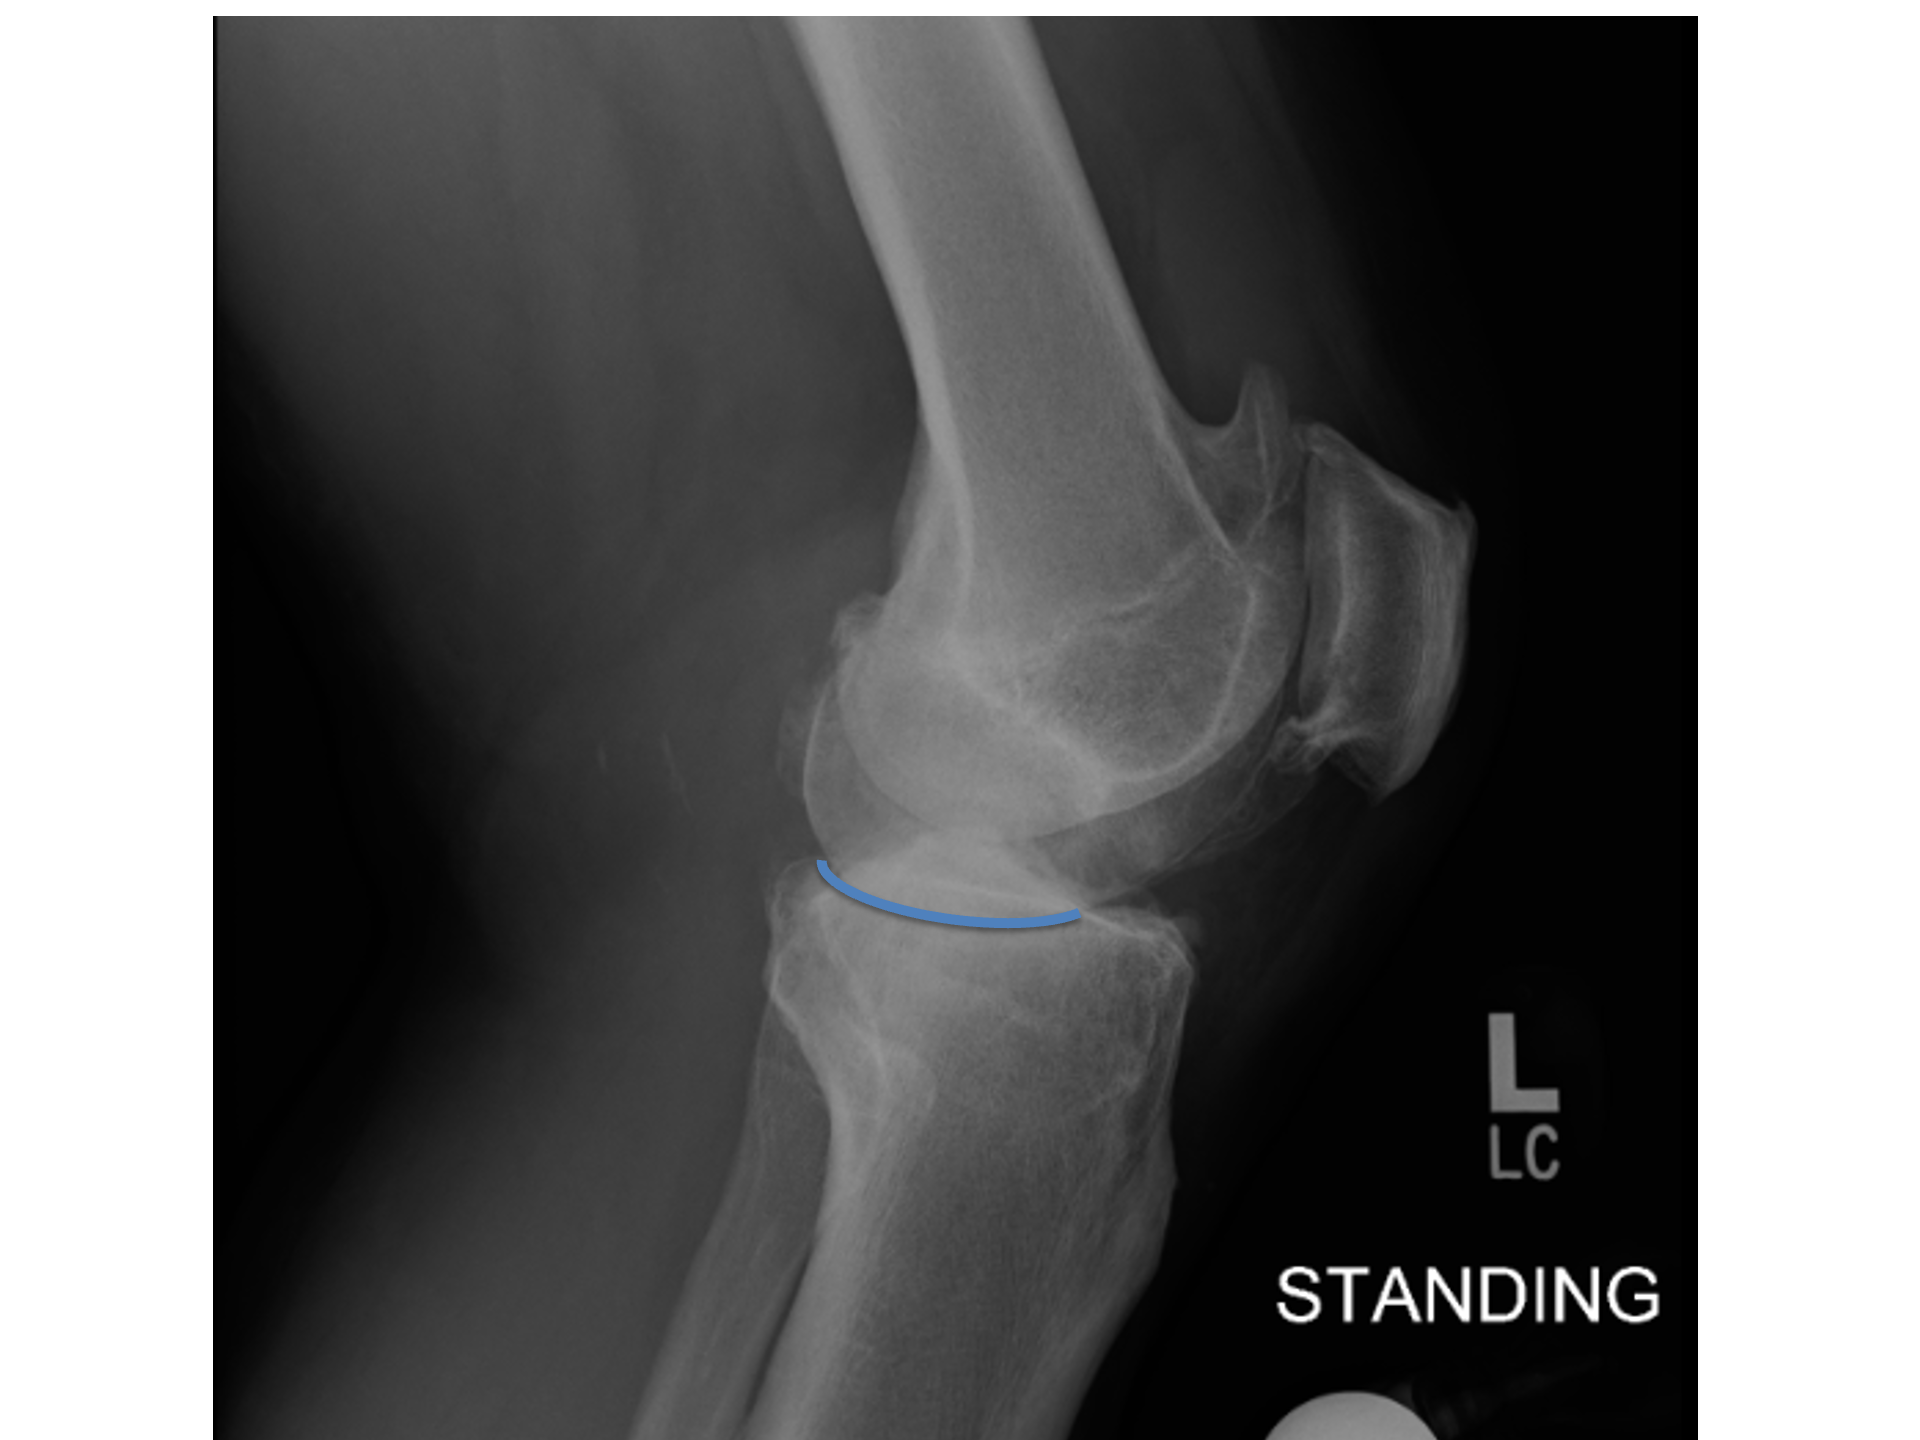

See that blue line of cartilage loss

..it curves up at the back.

The cartilage at the back of the knee remains intact.

AND a successful partial knee replacement relies on:

An intact Anterior Cruciate Ligament (ACL), and

An intact Medial Collatoral Ligament (MCL) on the inside.

(..and FWIW an intact lateral and Patella compartment)

This Inside-front pattern of osteoarthritis- short-handed to Antero-medial OA- implies an intact MCL + ACL.

And with those criteria met Dai should get a quicker recovery AND a better overall result**

And that makes sense 'cos Dai's knee is going to function more like a normal knee.. with normal functioning ligaments controlling how his knee moves.